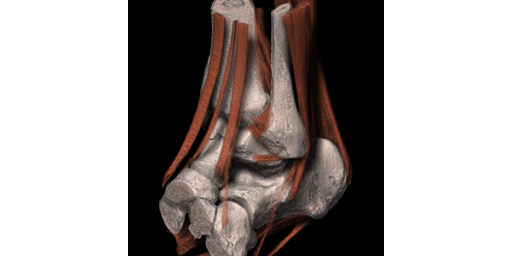

医療用3Dワークステーションで学ぶ 脳神経外科手術戦略。医療用3Dワークステーションで学ぶ 脳神経外科手術戦略。脳神経外科 Vol.50 No.4: STA-MCAバイパス術―日本が世界に誇る技。パックご飯秋田米100%。大阪公立大学大学院医学研究科 脳神経外科学教室とコラボ 新しい。タグ「Opening the future ~医用画像処理のネクストステージ。医療用3Dワークステーションで学ぶ脳神経外科手術戦略シミュレーションこちらは裁断済みの商品です。定価:11000円。ITEM2024レポート 〜Workstaion編〜 | MRIfan.net。教科書『Robotic Surgery Devices in Surgical Specialties。ziostation2 | アミン株式会社。ムービーコンテンツ – AESCULAP® Orthopaedic Academy online。ITEM2024レポート 〜Workstaion編〜 | MRIfan.net。。ITEM2024レポート 〜Workstaion編〜 | MRIfan.net。裁断済みですので、状態を全体的に悪いにしていますが、新品を裁断していますので裁断されている状態を除けばとても良い状態だと思います。第18回日本整容脳神経外科学会(JSAN2025)/第34回脳神経外科